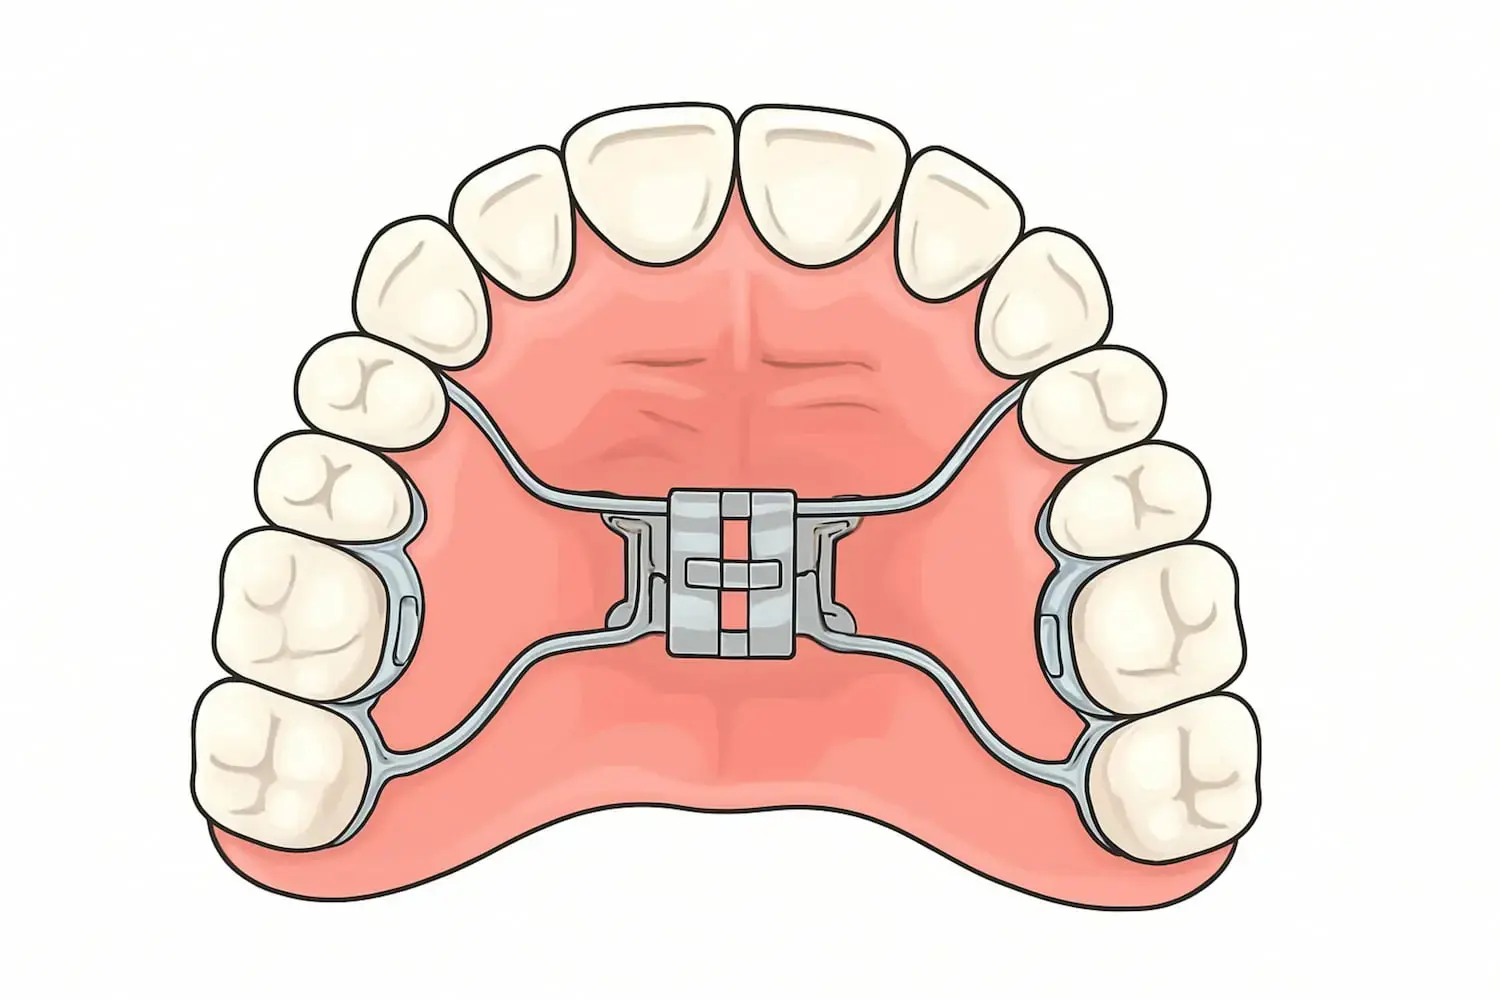

At Gianquinto Orthodontic Arts in Bakersfield, Tehachapi, and Mammoth Lakes, Dr. G provides expert care using automatic palatal expanders, a modern orthodontic device. This custom-made appliance is designed to gently and continuously widen the upper jaw without manual adjustments. By applying consistent, light pressure, the expander helps create enough space for proper tooth alignment and promotes a healthier, more functional bite.

Rapid Palatal Expander (RPE)

Bone-Borne Expanders

Miniscrew-Assisted RPE (MARPE)